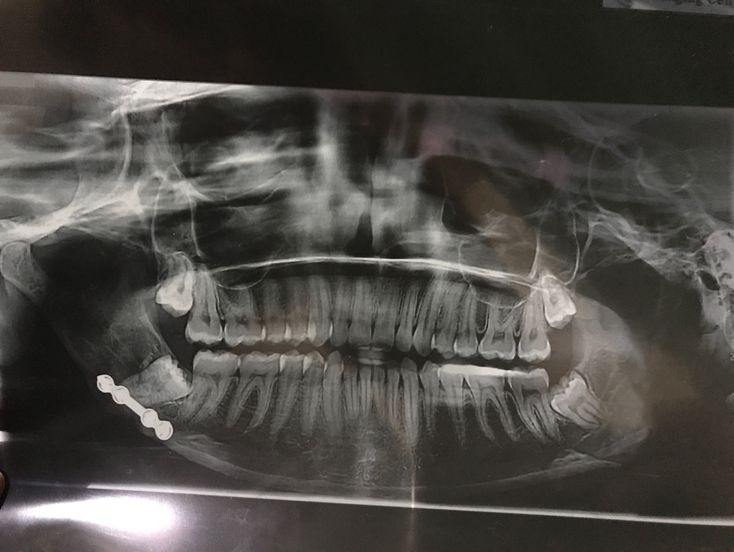

wht is the problem shown in this picture?? diagnose? treatment?

Impacted wisdom teeth. Surgical extraction.